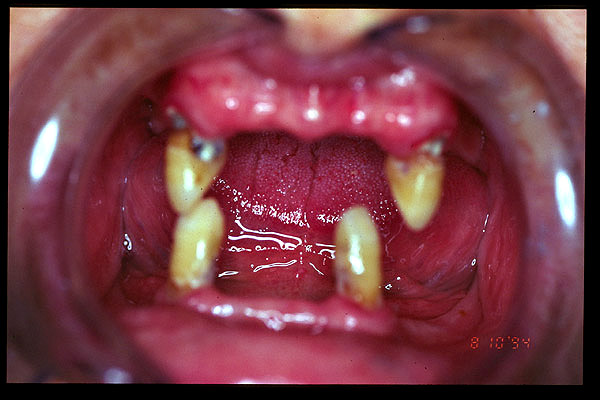

CM Ultimos dientes remanentes: los caninos